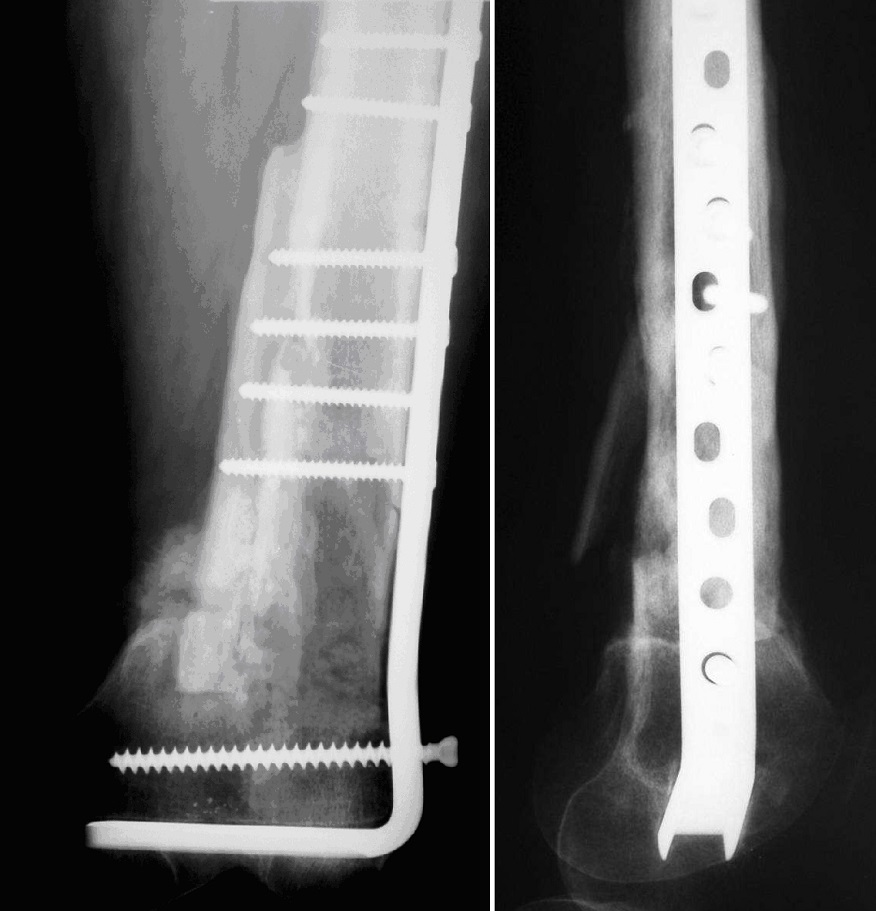

Paziente maschio, anni 74, pseudoartrosi femore distale sinistro.

Paziente maschio, anni 74, pseudoartrosi femore distale sinistro

Controllo a 3 mesi di distanza dopo osteosintesi con lama placca, innesto osseo contrapposto, cellule staminali autologhe e gel piastrinico

Controllo a 3 mesi di distanza dopo osteosintesi con lama placca, innesto osseo contrapposto, cellule staminali autologhe e gel piastrinico.